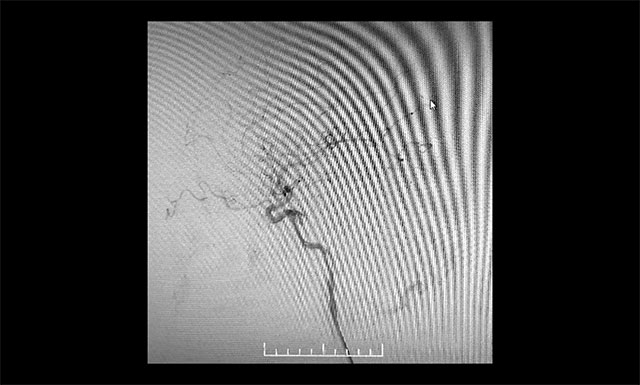

▲ 术毕左侧颈内动脉造影